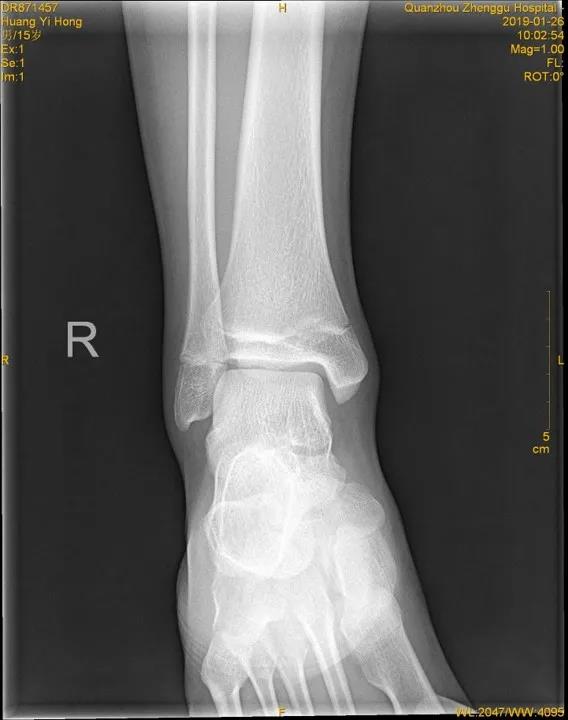

X线片:基本的辅助检查(应注意某些情况并非骨折)CT:能进一步检查隐匿性骨折或撕脱性骨折MRI:可检查肌腱、韧带的损伤肌骨超声:可代替或结合MRI检查软组织的损伤

X线

踝关节正位

踝关节侧位

儿童骨骺未闭